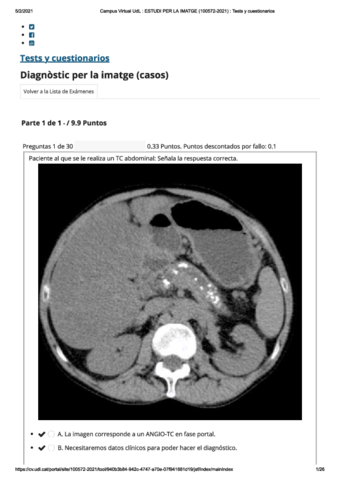

Exámenes - rayos-imagenes.pdf